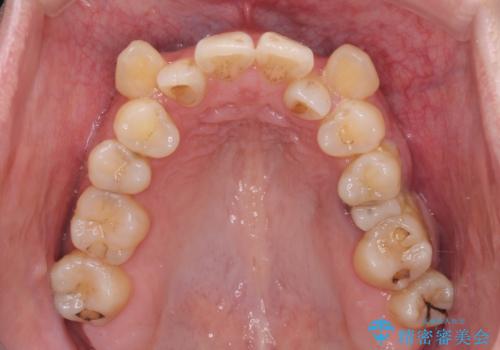

- 上下前歯のデコボコを気にして来院された患者様です。

デコボコが強いため、非抜歯で矯正をすると出っ歯仕上がりとなるため、上下左右の第一小臼歯4本を抜歯することとしました。

治療期間全体を通して歯の移動スピードがゆっくりであったので、当初予定よりも1年ほど長い、3年間を要することとなりました。